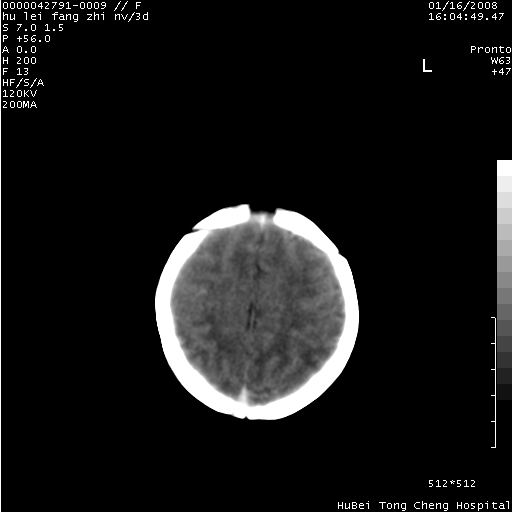

患儿 女,3天。惊跳,纳差。第二胎顺产,羊水ⅱ度。

临床诊断:hie?

颅脑ct轴位平扫(层厚、层距均为7mm),图像如下:

hie合并蛛网膜下腔出血

hie合并蛛网膜下腔出血,五、六脑室形成。

支持hie伴少量蛛血.